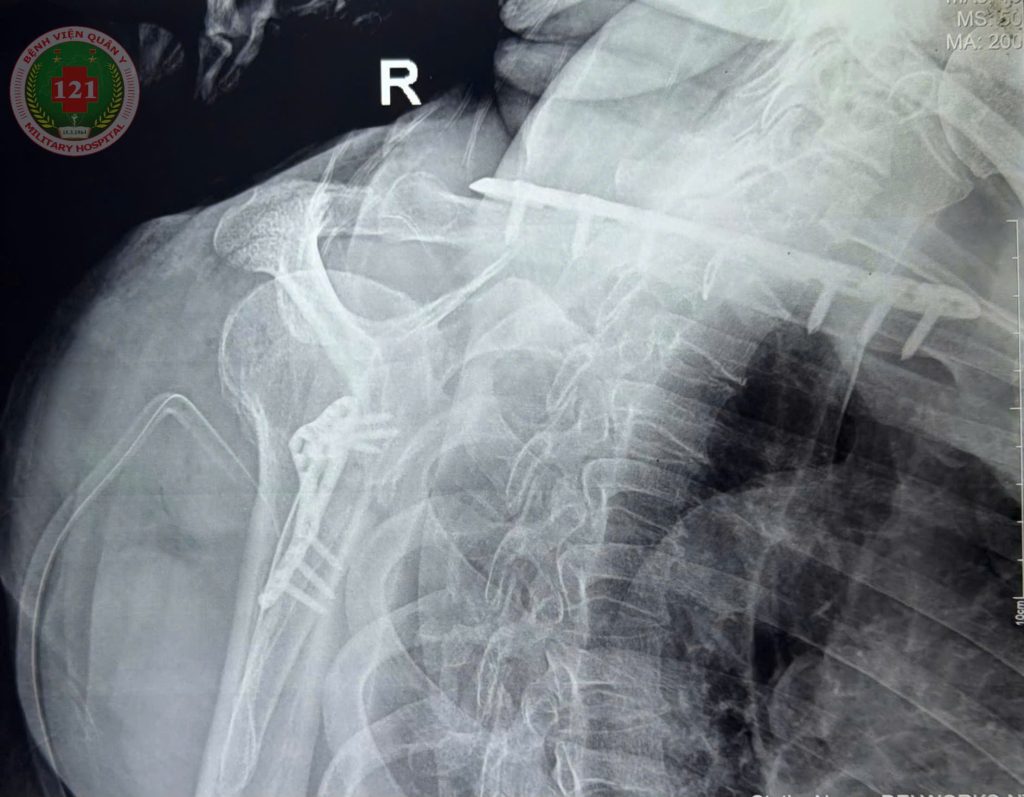

THỰC HIỆN THÀNH CÔNG CA PHẪU THUẬT NẸP VÍT KHÓA KẾT HỢP XƯƠNG BẢ VAI VÀ XƯƠNG ĐÒN CHO MỘT NAM BỆNH NHÂN 74 TUỔI

Ngày 24/01/2026, với sự hỗ trợ chuyên môn từ Bệnh viện Chấn thương chỉnh hình TP. Hồ Chí Minh, Bệnh viện Quân y 121 đã thực hiện thành công ca phẫu thuật nẹp vít khóa kết hợp xương bả vai và xương đòn cho một nam bệnh nhân 74 tuổi có tiền sử tăng huyết áp. Bệnh nhân nhập viện cách đây 09 ngày sau một vụ tai nạn giao thông, trong tình trạng vai phải sưng nề, bầm tím, vận động hạn chế. Bệnh nhân được chụp Xquang và chụp cắt lớp vi tính dựng hình 3D xác định gãy 1/3 giữa xương đòn phải, xương bả vai phải và 03 xương sườn. Sau khi được thăm khám và hội chẩn, các bác sĩ xác định cần tiến hành phẫu thuật nẹp vít khóa kết hợp xương bả vai và xương đòn để phục hồi chức năng vận động cho bệnh nhân.

Nhờ sự phối hợp chặt chẽ giữa đội ngũ bác sĩ Bệnh viện Quân y 121 và sự hỗ trợ kỹ thuật từ Bệnh viện Chấn thương chỉnh hình TP. Hồ Chí Minh, sau 03 giờ ca mổ đã thành công tốt đẹp, đảm bảo an toàn và tuân thủ đúng quy trình chuyên môn. Sau phẫu thuật, bệnh nhân có triển vọng phục hồi vận động sớm, giảm thiểu biến chứng và nâng cao chất lượng cuộc sống.